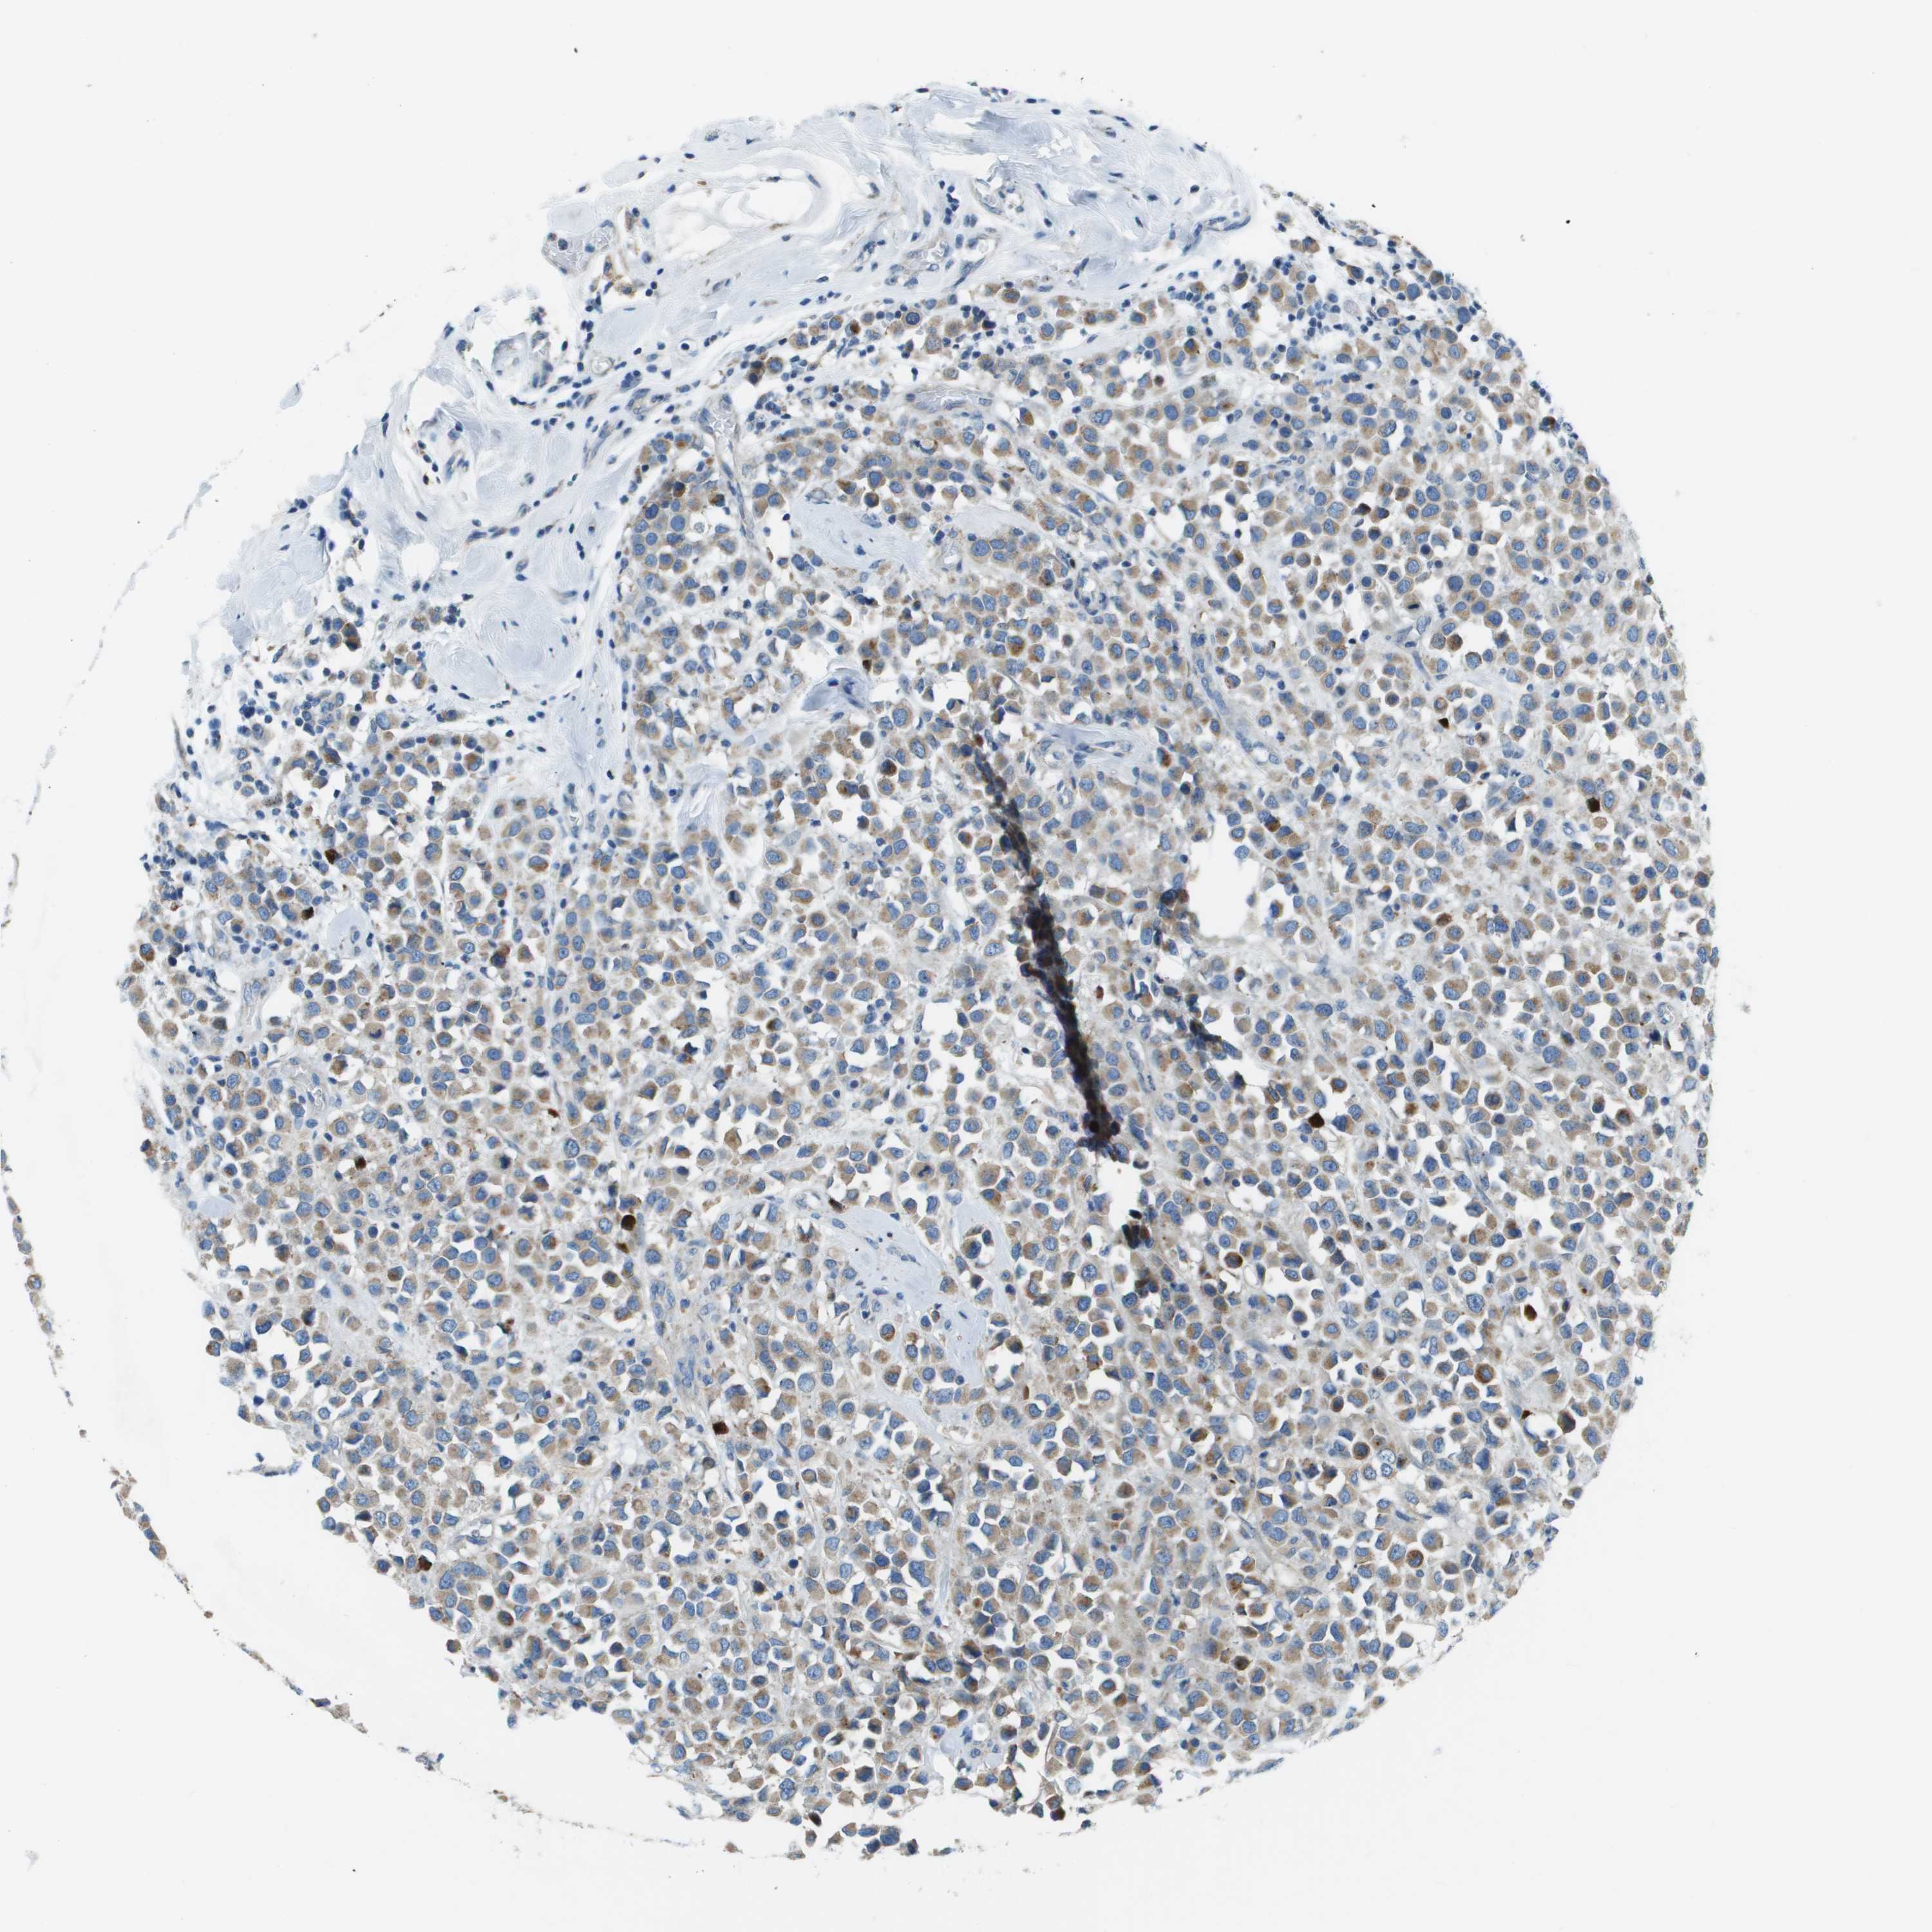

BRCA TCGA BRCA VALIDATION PROTEIN EXPRESSION

ANTIBODIES

AND

VALIDATION